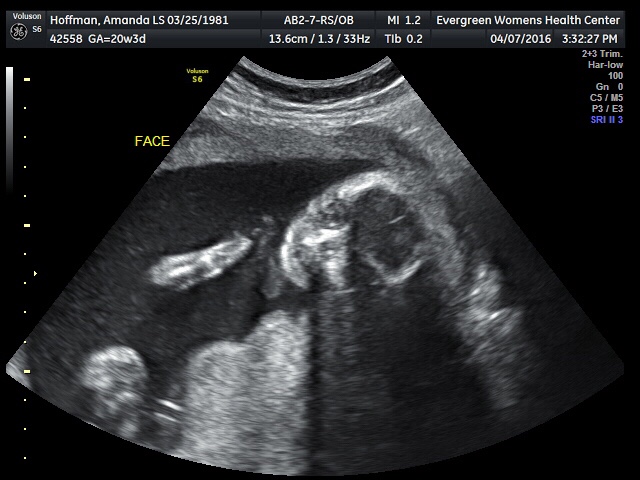

Day 1: ultrasound pic